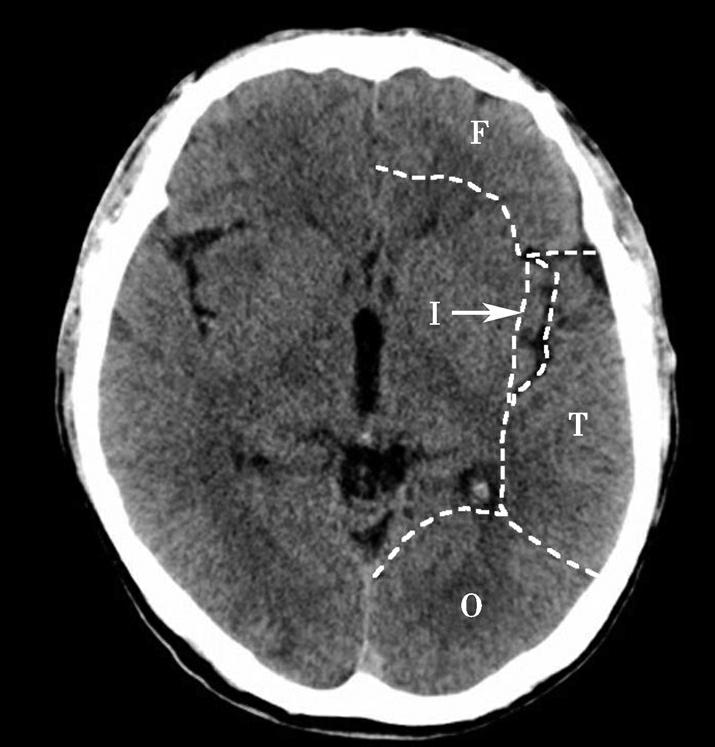

Alberta卒中项目早期CT评分(Alberta stroke program early CT score,ASPECTS)是一种评价急性缺血性卒中患者大脑中动脉供血区早期缺血性改变的简单、可靠、系统化的方法,是常用的脑卒中评定量表之一,可对缺血性病变快速进行半定量评价,有助于判定溶栓效果和远期预后。该评分主要基于CT平扫,具体分区如下(图1-2-76)所示,即选取大脑中动脉供血区2个层面。分区后共10个区域,每个区域记1分。评分时任何区域只要有低密度灶,则扣除该区域得分。正常脑ASPECTS评分为满分(10分),若MCA供血区广泛梗死累及全部区域时,则ASPECTS评分为0分。

图1-2-76 ASPECTS评分脑组织分区

A.在基底节层面(即丘脑和纹状体平面),分为各级分支M 1 、M 2 、M 3 、岛叶(缩写I)、豆状核(缩写L)、尾状核(缩写C)和内囊(缩写IC)后肢等7个区域;B.在基底节以上层面(基底节层面上2cm),包括M 4 、M 5 和M 6 。